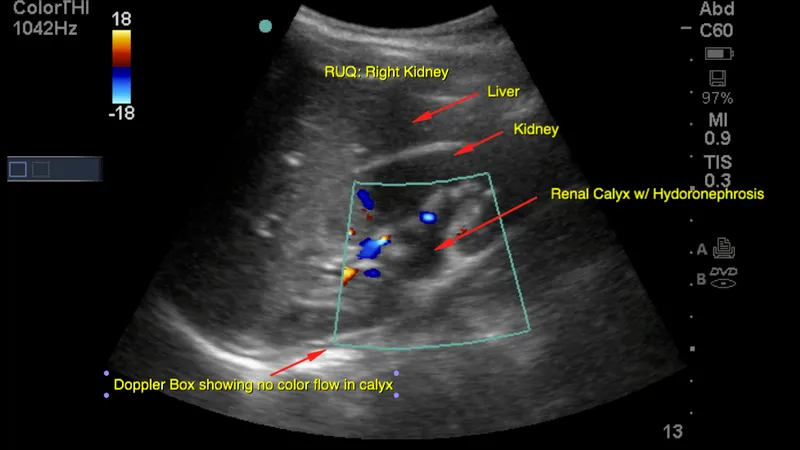

- Hydronephrosis: Dilation of pelvicalyceal system. Graded I-IV. Identify level & cause (e.g., stone, stricture, mass).

- Renal Calculi: Hyperechoic foci with posterior acoustic shadowing. 📌 Twinkling artifact on color Doppler is a key sign.

- Kidneys: hydronephrosis, stones (echogenic + shadowing), cysts.